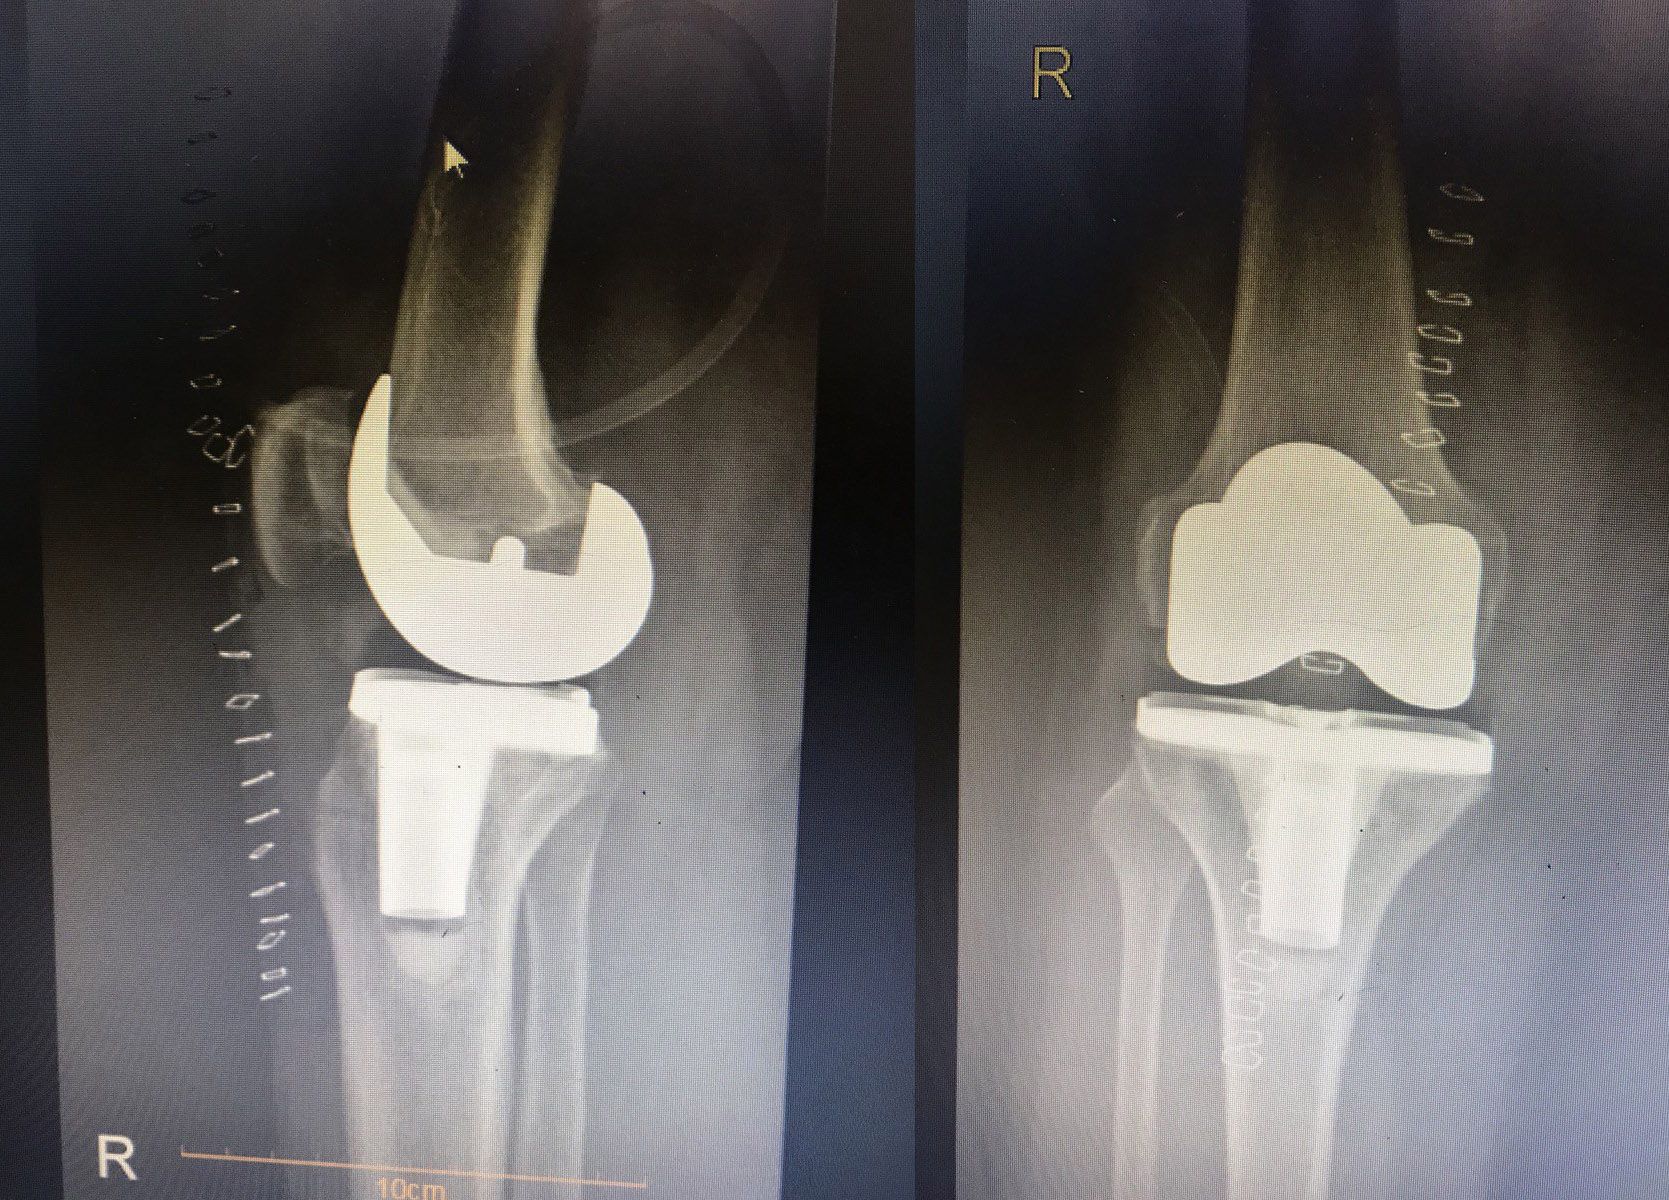

Diz artroplastisi ameliyatı

Diz eklemi ve patellanın değiştirilmesi

Diz eklemi protezi ameliyatının temel amacı, diz ekleminde ciddi hasar ve bozulma yaşayan kişinin yaşam kalitesini iyileştirmektir. Bu ameliyat, kişinin ağrısını azaltmasına, diz hareketini ve işlevini iyileştirmesine ve günlük aktivitelerini kolaylaştırmasına yardımcı olabilir.